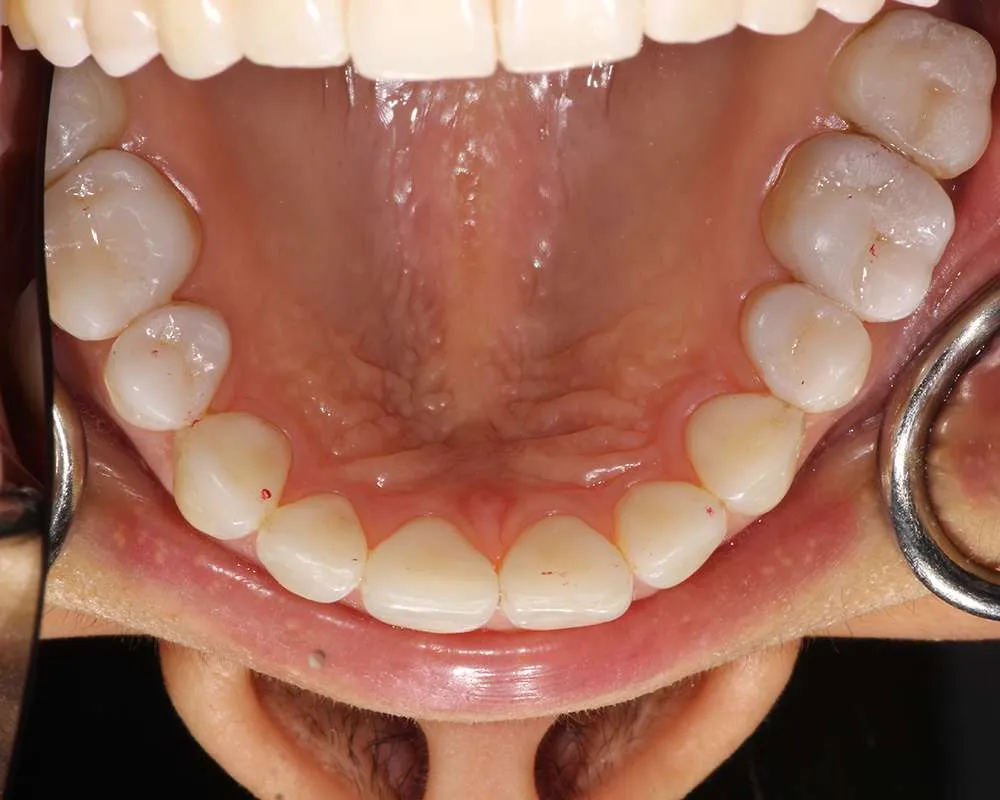

Real Stories, Real Results: Case Studies Showcasing How Our Personalized Approach Transforms Smiles and Lives

Witness the Remarkable Changes We Can Achieve